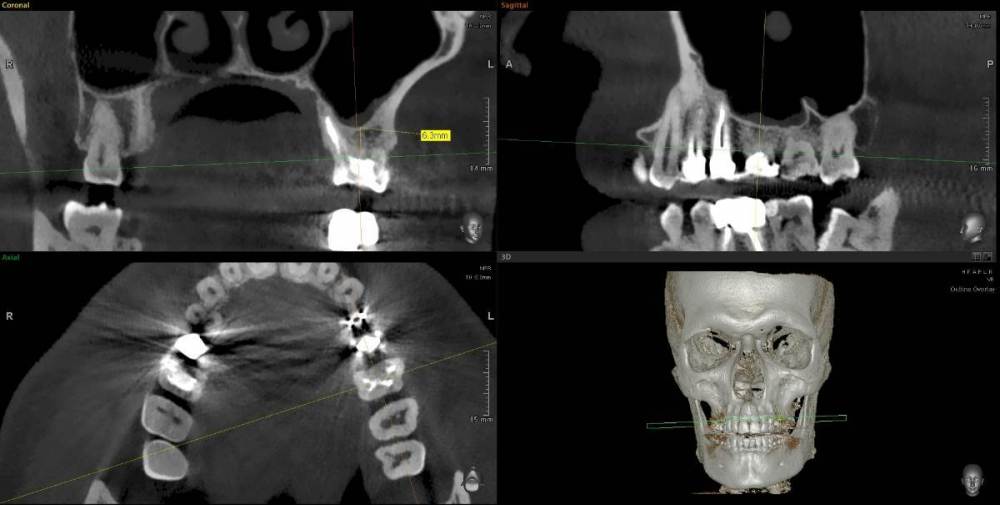

ict Опубликовано 18 января, 2023 Поделиться Опубликовано 18 января, 2023 зуб 2.6, в канале стекловолоконный штифт. Что лучше делать - вынимать штифт, перепломбировать каналы и на вкладку коронку или выдернуть зуб и имплант? Кость не очень высокая - какие могут быть проблемы с установкой импланта? Достаточно ли будет подсыпать костного материала или что-то сложное - открытый синуслифтинг? Ссылка на комментарий

ict Опубликовано 20 января, 2023 Автор Поделиться Опубликовано 20 января, 2023 (изменено) Большое Спасибо! Решил удалить, как заживет поменять пломбу на 2.7 (Вы абсолютно точно определили проблему с 2.7) и потом имплант. Склонился к удалению потому, что стоимость перелечивания сравнима с имплантом и вероятность успешного перелечивания без микроскопа невысока. В корне с гранулемой два канала, дополнительный с собственным отверстием (выщерблина на верхушке) без рентгеноконтрастного материала, вероятно не запломбирован. Пломба на 2.6 скололась месяца 3 назад скорее всего стала подтекать в канал, гранулема подросла, чувствительность в щеке уменьшилась (канал нерва над верхушкой виден). Будет обидно, если гранулема не уйдет Изменено 20 января, 2023 пользователем ict Ссылка на комментарий